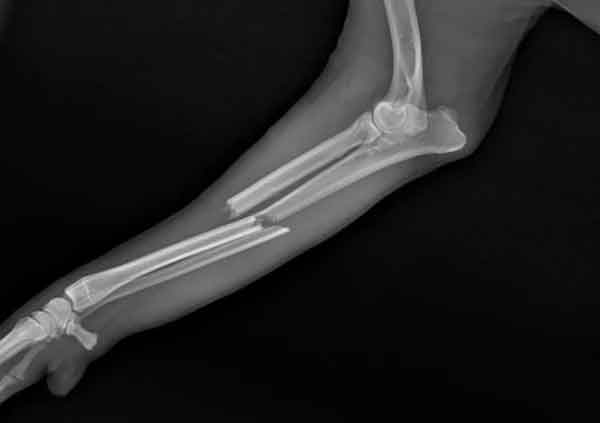

Digital X-Rays

Our state of the art digital X-ray machine allows us to process and examine X-ray images of your pet quickly, aiding in diagnosing and treating a variety of conditions. Occasionally we will even utilise X-ray in order to determine levels of dental disease in your pet.

It is not unusual for sedation to be necessary for your pet in order to be X-rayed – but be assured that we will discuss the chances of this with you beforehand.